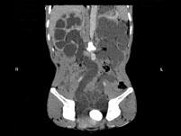

- 多项选择题男,33岁, 反复尿频,尿急, 尿痛3年余,排尿困难4月, 尿常规:蛋白(+), 红细胞0~1个/HP,白细胞(++), CT扫描如图所示,下列诊断哪项正确 ( )

A、膀胱结石

B、膀胱慢性炎性肉芽肿

C、膀胱癌

D、双侧肾积水,双侧输尿管扩张

E、膀胱多发性假性憩室